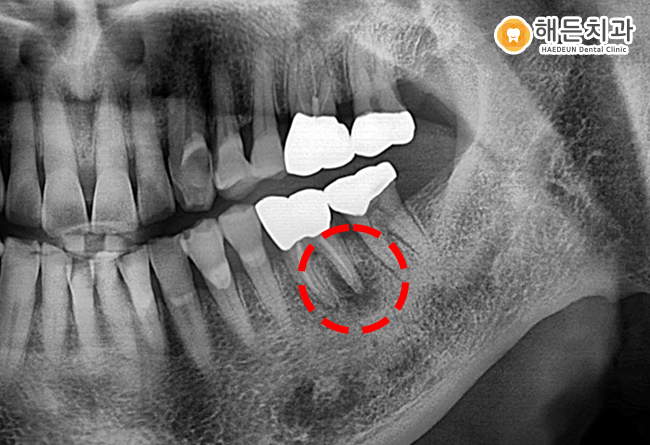

환자분은 또한 남은 치아를 보존하기 어렵다고 판단하여 발치를 계획하여 진행하도록 하였습니다.

천안아산치과 해든치과에서 임플란트 식립을 위해 말끔히 발치한 파노라마 사진입니다.

발치 후에 염증이 나타나 잇몸뼈가 많이 녹아있는 모습이 더욱 잘 나타나 있습니다.